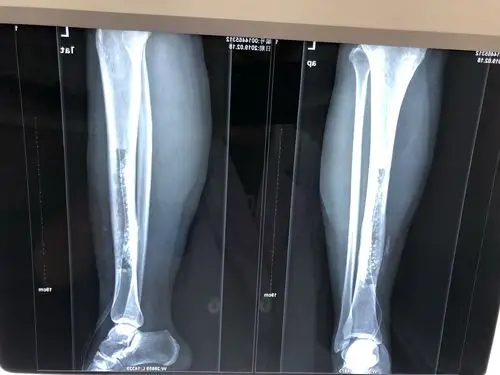

左胫骨慢性骨髓炎

这一例胫骨慢性骨髓炎大家有啥好建议